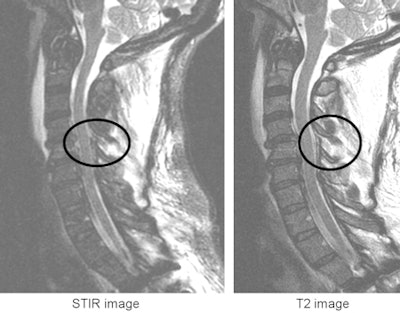

![]() |

| MRI identified a posterior ligament injury, and the patient ultimately underwent surgery. All images courtesy of Dr. Mitchel Harris. |